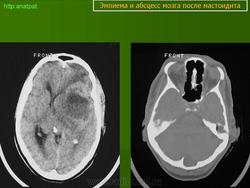

Абсцесс головного мозга – это очаговое скопление гноя в мозговом веществе, окруженное капсулой.

Абсцессы могут локализоваться в различных участках мозгового вещества. Обычно абсцессы сочетаются с менингоэнцефалитами, энцефалитами, сопровождаются повышением температуры тела, воспалительными изменениями крови и ликвора. Клиническая картина разнообразна и состоит из различных сочетаний общемозговых симптомов (головной боли, головокружения, тошноты, рвоты, нарушений сознания), менингеальной (оболочечной) и очаговой неврологической симптоматики.

Компьютерная (КТ) или магнитно-резонансная (МРТ) томография головного мозга являются ведущими методами диагностики посттравматических абсцессов, позволяющих судить об их расположении, объеме, структуре, консистенции, содержимом, воздействии на вещество головного мозга. Для исключения опухолей головного мозга, туберкулом, паразитарных заболеваний проводится ОФЭКТ (однофотонная эмиссионная компьютерная томография).